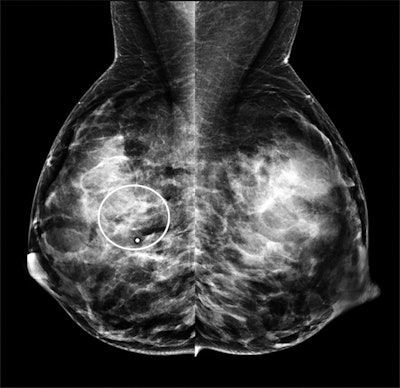

Craniocaudal mammogram from the same 40-year-old patient with invasive ductal carcinoma. The patient's mammogram images show a subtle, obscured mass at the site of the palpable abnormality (region of interest) with some associated amorphous calcifications.

Mediolateral oblique mammogram from the same 40-year-old patient with invasive ductal carcinoma. Both mammograms depict heterogeneously dense breast tissue.The authors attributed mammography's lower specificity due to the modality's struggle depicting cancers in dense breast tissues during pregnancy and lactation. Notably, 98% of the patients in the study had dense breast tissue, including 72% of whom had extremely dense breast tissue.